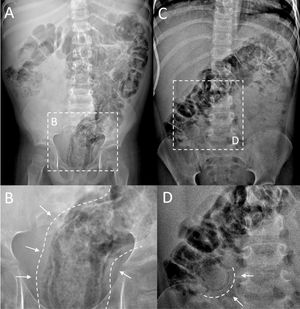

Presentamos 2 casos de neumatosis intestinal (NI) mural diagnosticada por radiografía simple de abdomen en pacientes receptores de trasplante alogénico de progenitores hematopoyéticos (TPH), en tratamiento inmunosupresor por enfermedad injerto contra receptor aguda (EICRa) con participación digestiva. El primero, de 5 años, ingresado a 51 días post-TPH, EICRa con buena evolución con tratamiento con micofenolato, corticoterapia y fotoféresis extracorpórea, presenta distensión abdominal súbita (fig. 1 A y B). El segundo, de 6 años, en el día +71 de un segundo TPH, en tratamiento con micofenolato y corticoterapia, consulta por estreñimiento y dolor abdominal, asociando distensión abdominal a la exploración (fig. 1C y D).

Radiografías de abdomen simple. En el primer paciente (A) se observa extensa neumatosis, más evidente en colon descendente y recto-sigma. Imagen ampliada de región pélvica (B) donde se definen con claridad las áreas lineales de densidad aire en disposición paralela a la luz rectal, compatible con gas mural. En el segundo paciente (C) se observa afectación en hipocondrios y epigastrio caracterizada por distensión de la luz intestinal superpuesta a múltiples imágenes de gas mural menos evidentes. En la imagen detallada del mismo paciente (D) se observa imagen aérea curvilínea, correspondiendo a zona de neumatosis mural mejor definida.